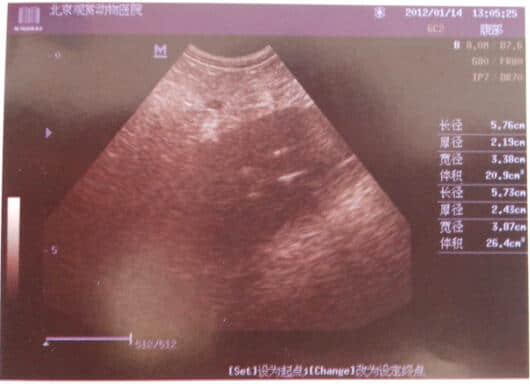

3.2 B超检查如下

从血液化验结果可发现WBC较高达42.62,血清脂肪酶高达4763,而淀粉酶却在正常值,这说明该犬胰腺炎已发病48或72小时以上。并据B超结果和临床症状可诊断为急性胰腺炎、脂肪肝和少量膀胱结石。其以胰腺炎为主。由于血糖较高不排除有糖尿病,建议复查血糖、尿糖。